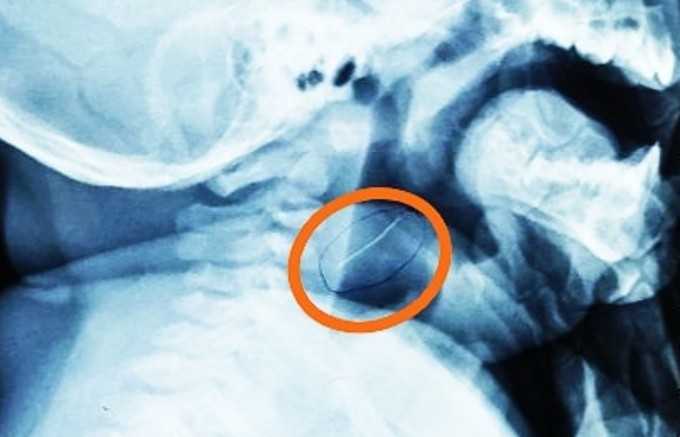

TP HCM - Ăn phải sợi kim loại sắc nhọn dài 2 cm sót trong tô cháo cá, bé trai 8 tháng tuổi bị thủng hạ họng, may cấp cứu kịp thời.

Dị vật gắp ra không phải xương cá mà là một sợi kim loại mảnh, rất cứng và nhọn hai đầu, dài gần 2cm, bác sĩ Trần Thiện Nhơn, khoa Tai Mũi Họng, ngày 29/1 cho biết. Sợi kim loại này đang cắm sâu vào vùng hạ họng bệnh nhi, may mắn là chưa đâm quá sâu nên tính mạng em bé không gặp nguy hiểm.

Sợi kim loại găm sâu vào họng cháu bé trước khi được lấy ra. Ảnh: Bệnh viện cung cấp.